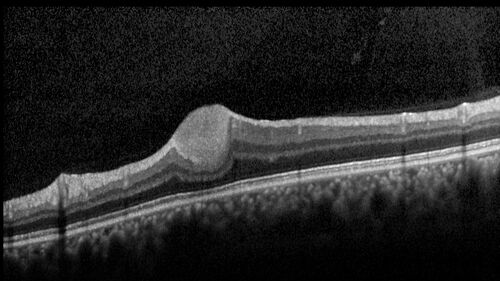

Astrocytoma (Astrocytic Hamartoma) no calcification

38 year old man with no symptoms